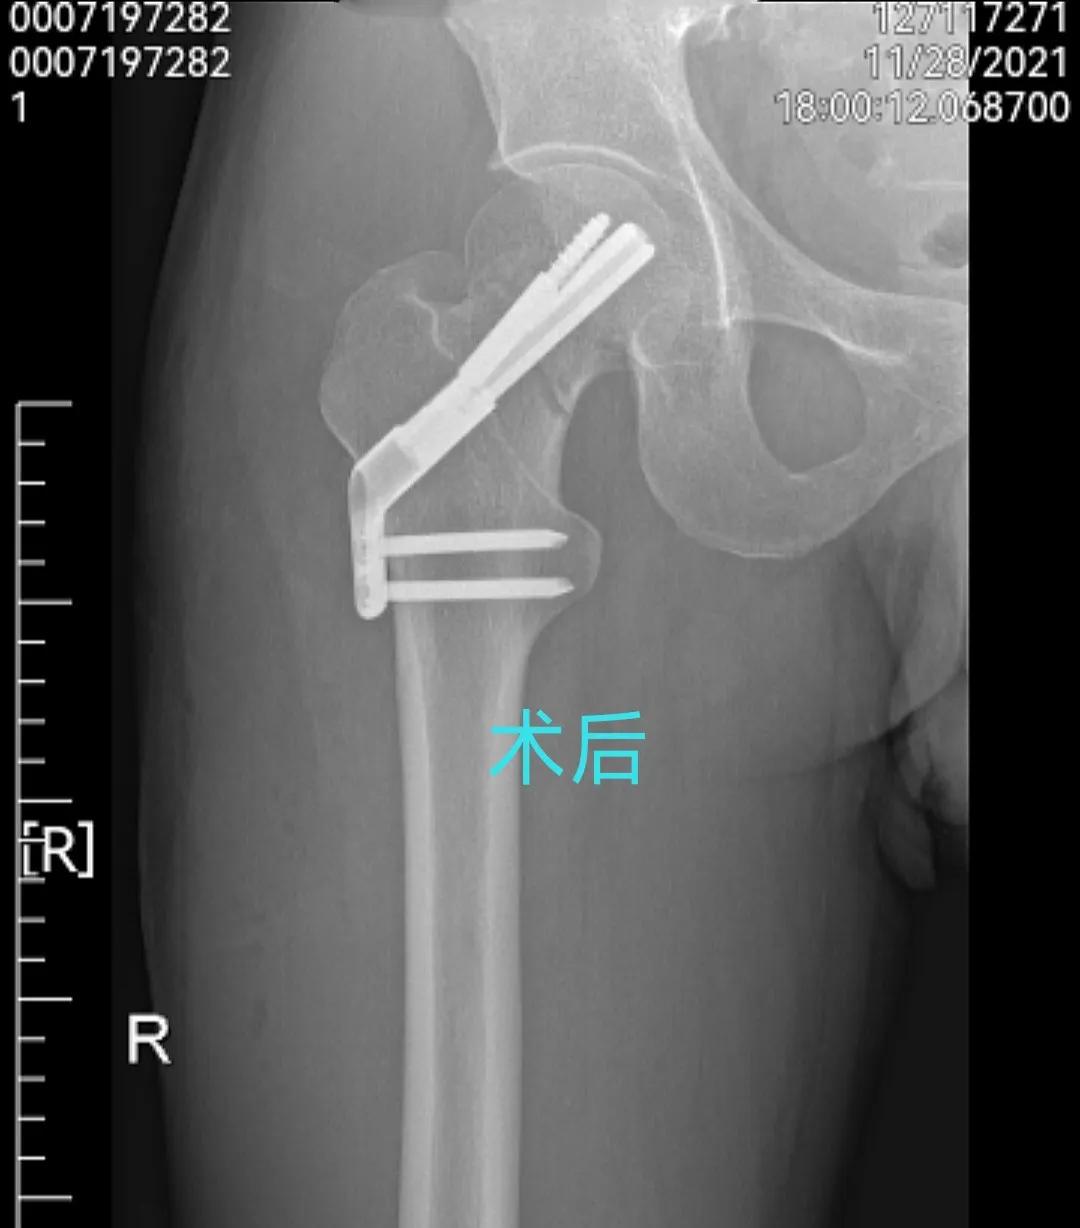

然后的然后,当时也不知道过了多久,慢慢的有了意识,有意识后首先发现自己被扒的一丝不挂,只是在*体下**位置盖一白色浴巾,两个护士小姐姐拿着热风管在我身体上来回的吹热风,然后我微微动了下伤腿,发现没有术前那么疼了,可能是麻醉还没过去原因。记得大概过了半小时左右,把我推出了手术室,送回了病房!然后主治医师进来了,拿着手术室的透视片给我说:手术很成功,骨折端复位很好,基本上都看不到骨缝了.我当时也没细看,再说也看不懂,就只说了声谢谢医生,辛苦了!然后简单的交代了一下,就走了,也没交代让我穿丁字鞋,夹枕头等等…大约又过了半小时左右,进来两名护士,给我拔掉了引流管与尿管!输上了液体,罩上了氧气,夹上了心电图…这个过程持续了一晚上…

图(3)术后x片